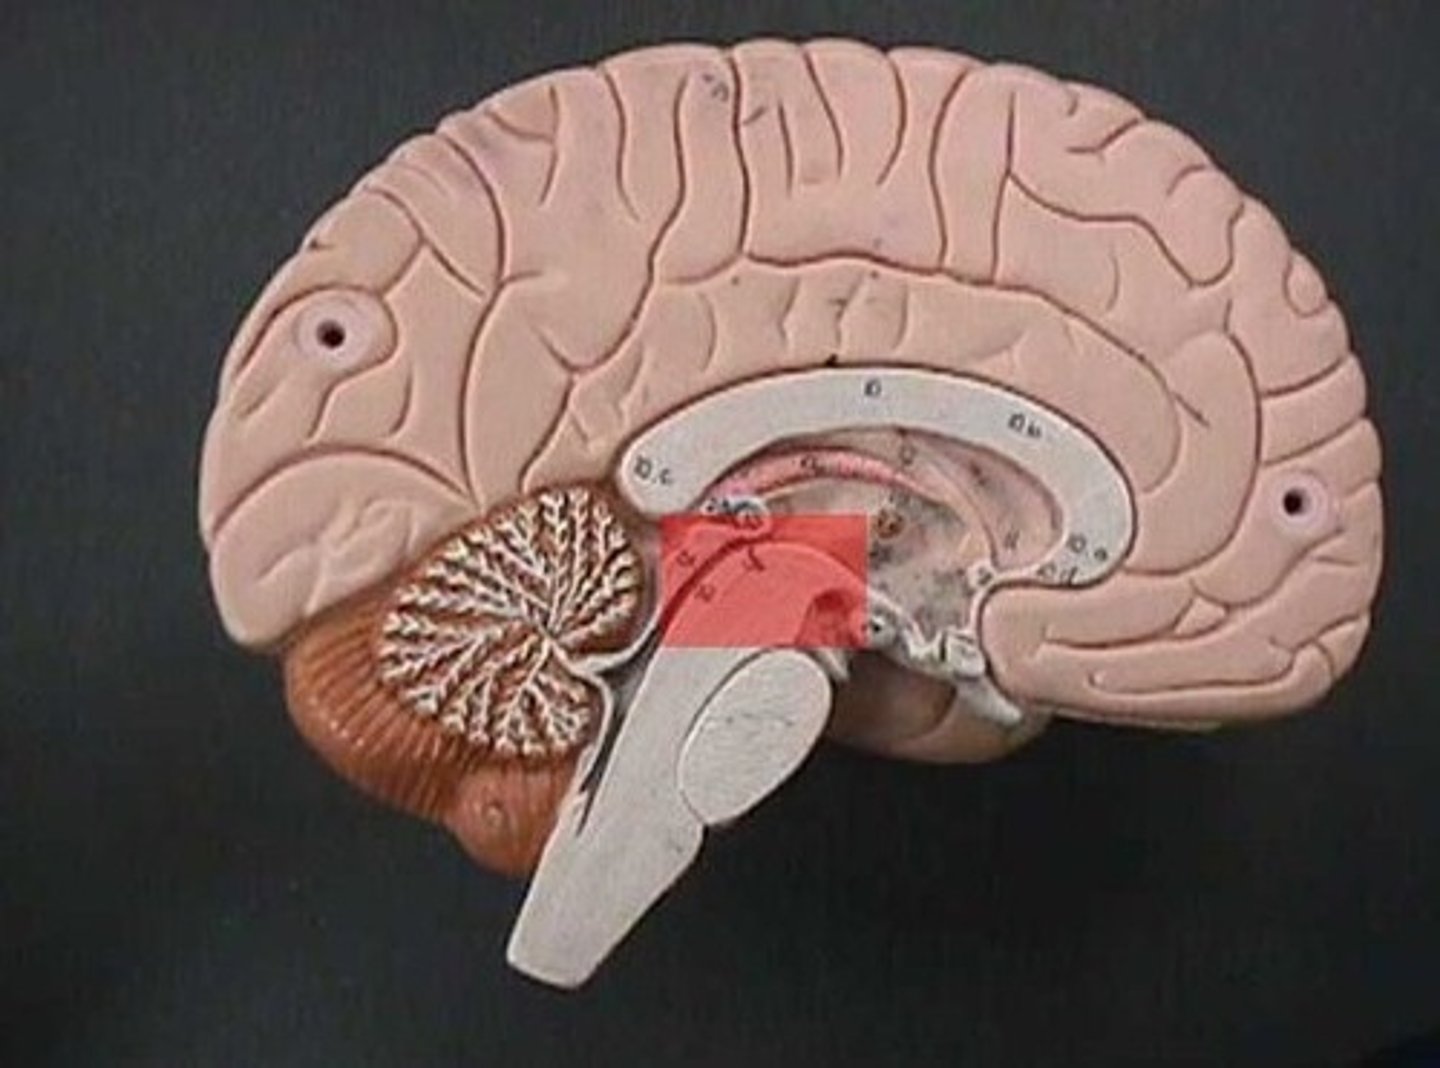

midbrain

A small part of the brain above the pons that integrates sensory information and relays it upward.

corpora quadrigemina of midbrain

coordinates visual and auditory reflexes

superior colliculus of midbrain

receives visual sensory input

inferior colliculus of midbrain

receives auditory sensory input

pons

contains sensory and motor tracts that connect brain to spinal cord

brainstem nuclei, respiratory muscles (rhythm)

medulla oblongata

brainstem nuclei, vital centers for control

of respiratory rate and cardiac function (heart rate/strength)

has sensory and motor tracts

gagging and vomiting center

cerebellum function

fine tuning of skilled voluntary motor activity to produce smooth, accurate movements

balance, equilibrium, and skilled movement